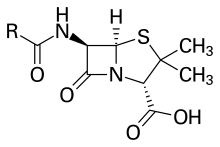

Lipoic acid, an essential cofactor of four mitochondrial enzyme complexes. Penicillin core structure, where "R" is the variable group.

Penicillin core structure, where "R" is the variable group.

Not all organosulfur compounds are foul-smelling pollutants. Penicillin and cephalosporin are life-saving antibiotics, derived from fungi. Gliotoxin is a sulfur-containing mycotoxin produced by several species of fungi under investigation as an antiviral agent. Compounds like allicin and ajoene are responsible for the odor of garlic, and lenthionine contributes to the flavor of shiitake mushrooms. Volatile organosulfur compounds also contribute subtle flavor characteristics to wine, nuts, cheddar cheese, chocolate, coffee, and tropical fruit flavors.[28] Many of these natural products also have important medicinal properties such as preventing platelet aggregation or fighting cancer.